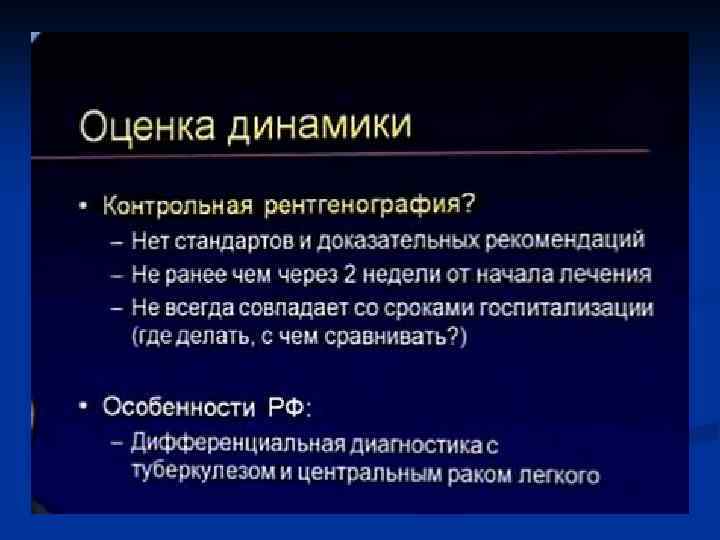

Показания к КТ грудной клетки n n n Недостаточная диагностическая информация стандартного рентгенологического исследования с наличием клиниколабораторных данных при подозрении на пневмонию Стертые клинические и лабораторные данные у больных с подозрением на пневмонию Затянувшийся кашель, субфебрилитет у больных с ОРВЗ Обострения хронических заболеваний бронхо-легочной системы Осложнения в процессе лечения больных пневмонией Затянувшиеся пневмонии